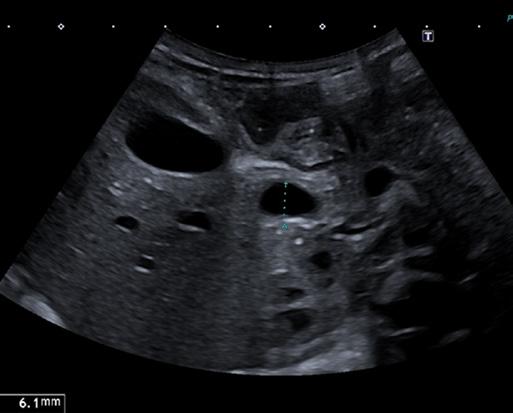

T. è una bambina nata prematura a 32 settimane. Trasferita in TIN per distress respiratorio da aspirazione meconiale, viene trattata con fototerapia per la scoperta di iperbilirubinemia. A causa della persistenza dell’ittero esegue esami del sangue per escludere patologie infettive, tiroidee e deficit di cortisolo. Screening neonatale e indici di emolisi negativi. Dosaggio dell’alfa-1 antitripsina normale [1]. Viene dunque trasferita presso il reparto di epatologia del Necker di Parigi per le cure del caso. Gli esami evidenziano una colestasi a GGT elevate e citolisi epatica (AST 227 U/L, ALT 202 U/L, GGT 516 U/L, BT 8,5 mg/dl BC 7,6 mg/dl). All’ecografia epatobiliare eseguita a digiuno da 6 h si evidenzia una colecisti non atresica [Figura 1], anzi, piuttosto distesa con all’interno sludge biliare, dilatazione della via biliare extraepatica [Figura 2] con evidenza di calcolo a livello della porzione distale coledocica [Figura 3] e dilatazione delle vie biliari intraepatiche, che presentano un aspetto irregolare. Assenza di polisplenia. Davanti alla presenza di un calcolo incuneato, viene avviata terapia iperidratante con aggiunta di UDCA, supplementazione vitaminica ADEC e vit K ev [2]. All’ecografia di controllo non si evidenzia più la litiasi biliare. Nuovo ricovero dopo 6 giorni per la persi-

Figura

Figura 1. Colecisti non atresica distesa con all’interno sludge biliare.

Figura 2. Dilatazione dilatazione della via biliare extraepatica di 6 mm.

Figura 3. Calcolo incuneato a livello della porzione distale coledocica.